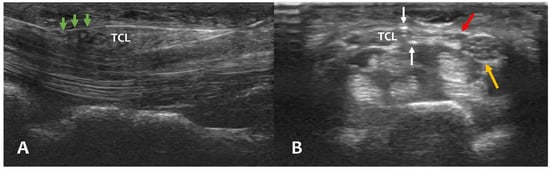

2.2.3. Surgical Procedure